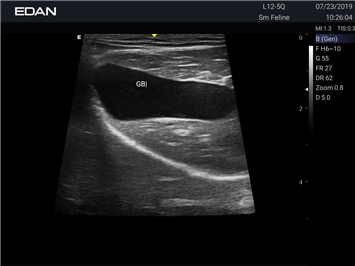

EDAN Acclarix AX2 VET

Ветеринарный ультразвук одним нажатием. Система Acclarix AX2 VET разработана с целью обеспечить бескомпромиссную производительность по доступной цене. Наличие уникальных двойных аккумуляторов в легком корпусе массой 4,5 кг из магниевого сплава позволяет системе Acclarix AX2 VET удовлетворять все потребности ветеринарных исследований, сохранив низкую стоимость.

EDAN Acclarix AX2 VET представляет собой специализированную ветеринарную ультразвуковую систему, сочетающую высокую производительность с доступной ценой. Благодаря продуманной конструкции и передовым технологиям, система обеспечивает качественную диагностику животных различных видов.

• Высокое разрешение для детальной диагностики

• Улучшенная визуализация глубоко расположенных органов